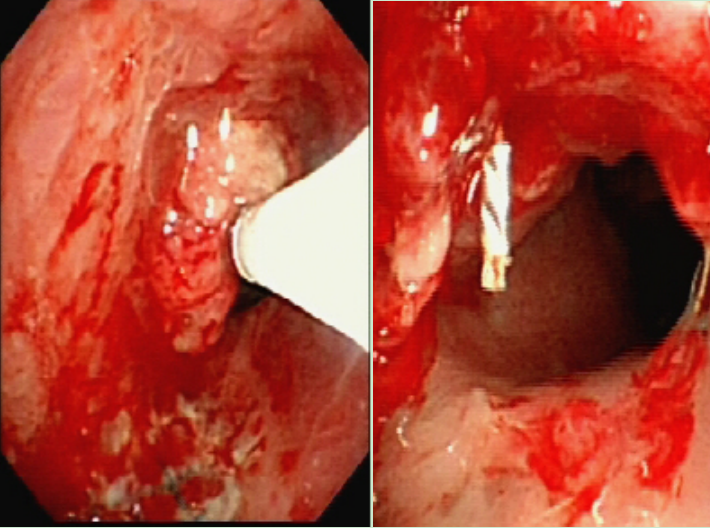

一、病情回顾:气道肉芽增生、手术遇阻 患者男性、20岁,因脑外伤在中信惠州医院救治。患者气管切口虽早已愈合,但言语声音低弱表述不清,休息状态下呼吸喘鸣声明显,稍有活动时呼吸喘鸣声更明显。医学影像中心喉部CT平扫+三维重建显示:1.喉咽左后壁肿胀增厚,相应喉腔变窄。2.环状软骨多发骨折,气管腔塌陷、变形且变窄。这些状况严重阻碍了患者的呼吸,使得即将进行的神经外科手术面临较大风险。 二、冷冻冻切+高压球囊协同“作战”,“抢修”生命通道 面对复杂紧急病情,呼吸医学中心介入团队迅速制定了详细的治疗方案。行无痛支气管镜检查和辅助喉罩通气术,术中迅速冻切肉芽组织,遂即患者呼吸的皮氧饱和度从60%升至正常范围。 卢晔教授表示,患者仰卧时呼吸困难,且术前三维重建发现肉芽组织“疯长”堵塞大气道,严重影响后续手术安全进行。为此,团队决定采取反复多次高压球囊扩张 + 反复冷冻冻切肉芽组织 + 冻融新鲜撕裂口的治疗方式。术中,利用冷冻冻切技术,短短几分钟内就将肉芽组织快速清除,使气道迅速达到基本通畅。同时,根据患者疤痕狭窄的程度和部位,精准选择不同直径、不同压力的球囊,进行恰到好处的扩张,确保手术安全。这项技术具有诸多显著优势。操作简便,易于学习掌握;重复性良好,能够根据患者具体情况灵活运用;损伤小,安全性高,可有效避免中央气道气肿和气胸的发生,对于疤痕致狭窄也不会引发大出血,为患者的治疗提供了有力保障。

呼吸内镜检查报告